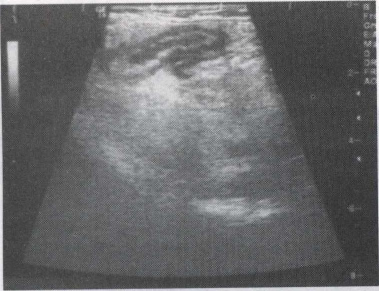

40.患者女,56岁,急性胰腺炎1周。B超图像如图,诊断为()